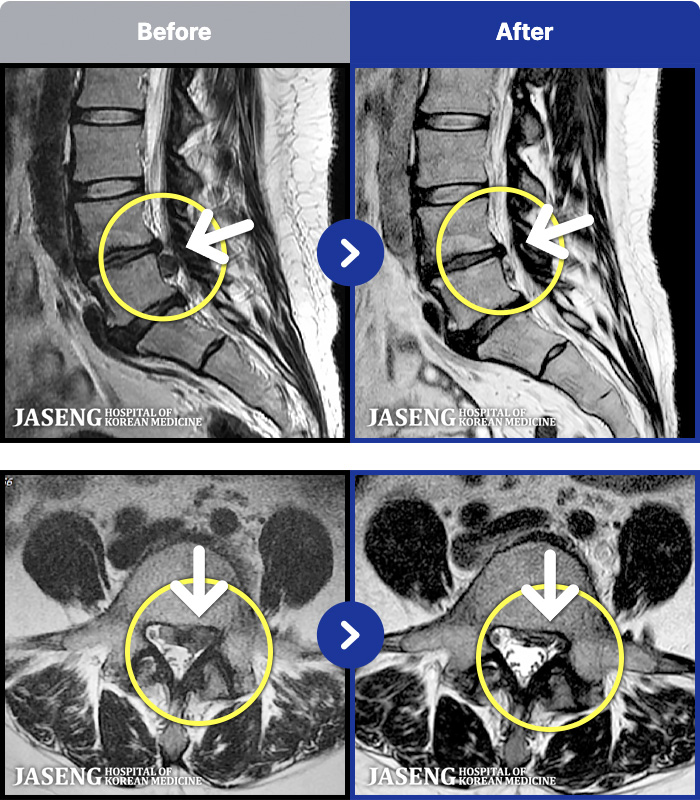

- MRI ġ

MRI ġ

MRI ũ ʸ Ȯϼ.